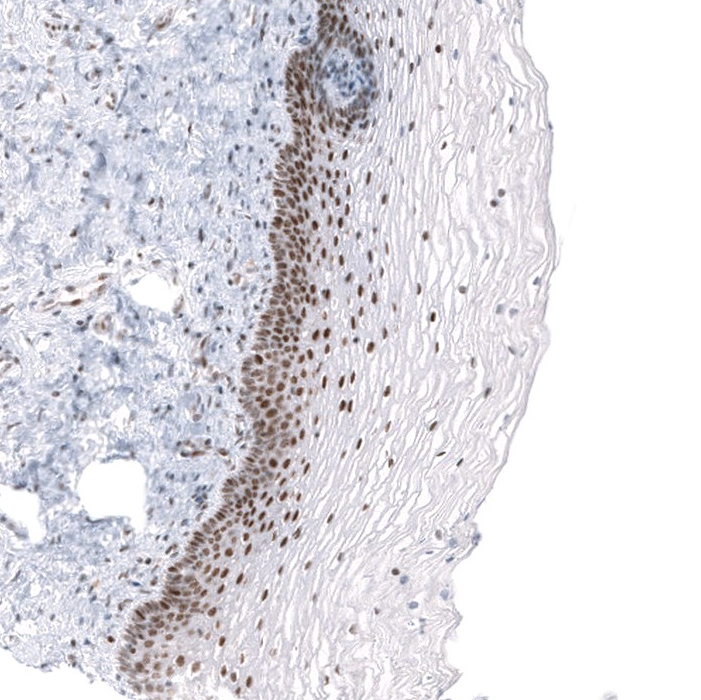

Immunohistochemical staining of human cervix shows strong nuclear positivity in squamous epithelial cells.